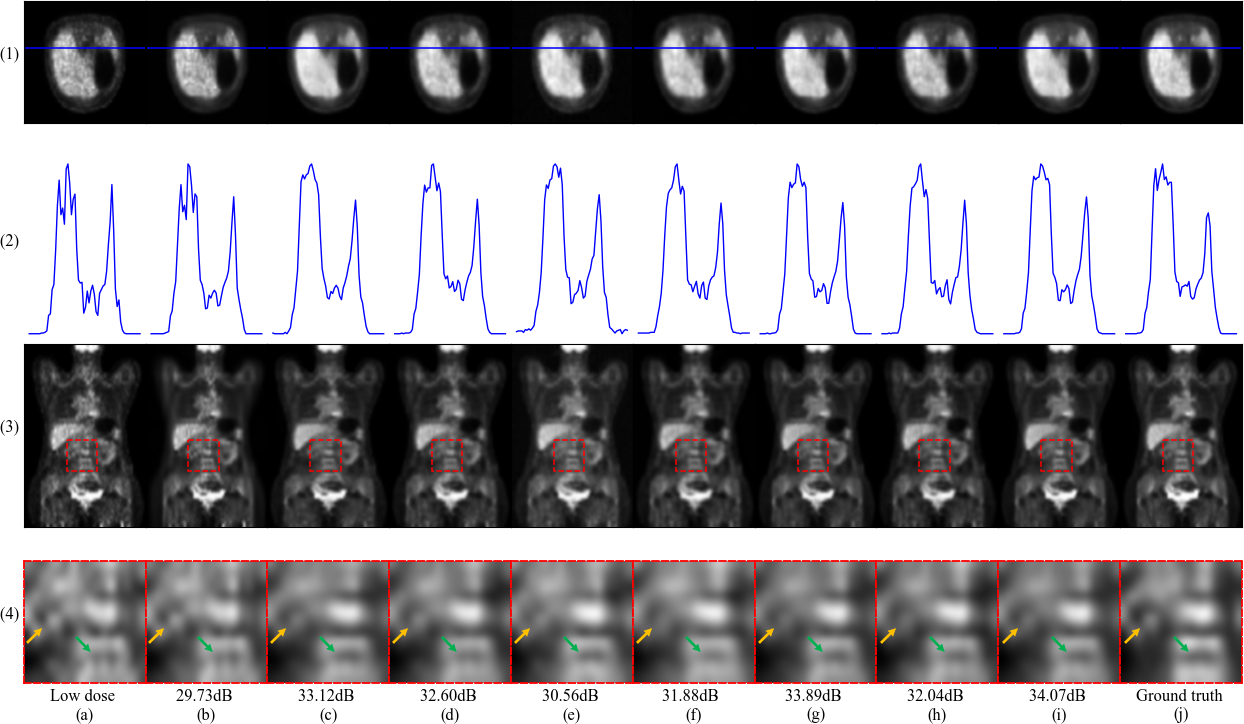

Example images synthesized from different approaches are shown in Fig. 4. Apparent noises still exist in the results of BM3D, 3D-Unet, 3D-cGAN and SGSGAN-3D-Unet (See Fig. 4, (1) and (2)). Images produced by 3D-cGAN and 3D-Unet are more blurry, where the anatomy and background are mixed together (See Fig. 4, (4)). By contrast, our framework can improve the sharpness of images and SGSGAN-DCITN gives the best visual effect among all.

AdaIN achieves more effective performance. It utilizes the learned styles to adjust the features and forces the generator to optimize through style modulation and try to bridge the style gap. Combining noise and AdaIN gives a more promising result. Fig. 6 shows the examples of using style modules. When adding noise only, the images become sharper and the bumps are more distinct. But some structures are still distorted compared with the ground truth. AdaIN could solve this problem to some extent. Columns (e) and (k) in Fig. 6 show that the networks with AdaIN could correct the distorting shape and achieve a better edge similarity. To sum up, applying two modules together leads to the best perceptual quality.